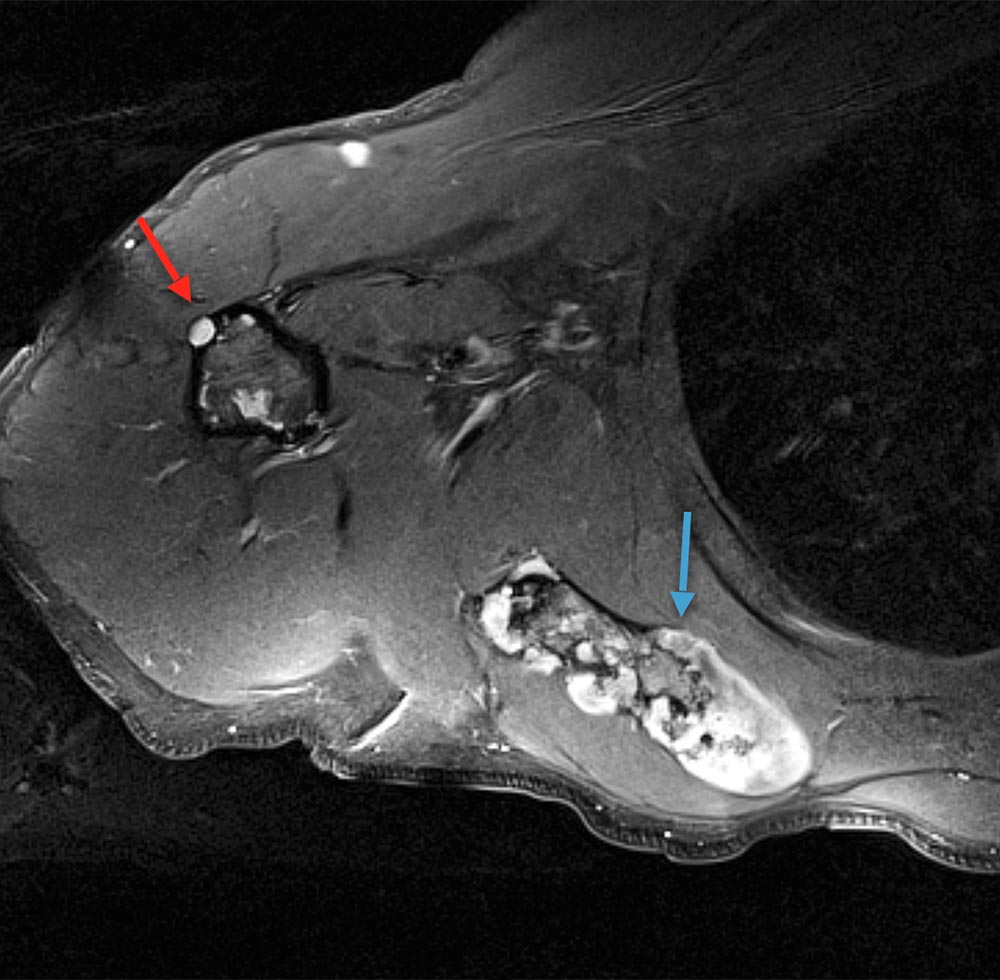

Maffucci syndrome is characterized by multiple enchondromas, often visible as circumscribed dermal distensions of fingers and/or toes in combination with spindle cell hemangiomas. Synonym: enchondromatosis Ollier-Maffucci.

The overgrowth in Maffucci syndrome is characterized by hard, yellowish, indolent skin protuberances (enchondromas) attributable to a bone and originating from dysplastic cartilage tissue. These can be unilateral or bilateral, but are usually clearly asymmetric. Depending on their location, enchondromas can cause growth reduction and curvature of affected limb segments. The forearms and lower legs are most commonly affected, but hands and feet are often affected as well.

The vascular changes in Maffucci syndrome are multifocal, dermal, bluish-reddish vascular nodules of the hypodermis (“spindle cell hemangiomas”) that are similar to, but histologically distinct from, a venous malformation.

Enchondroma foci may occur until adolescence, after which there are normally no new lesions, instead restitution in some cases is reported. Malignant degeneration of enchondromas to chondrosarcoma may occur in adulthood; the risk of degeneration is reported to be a maximum of 25%.